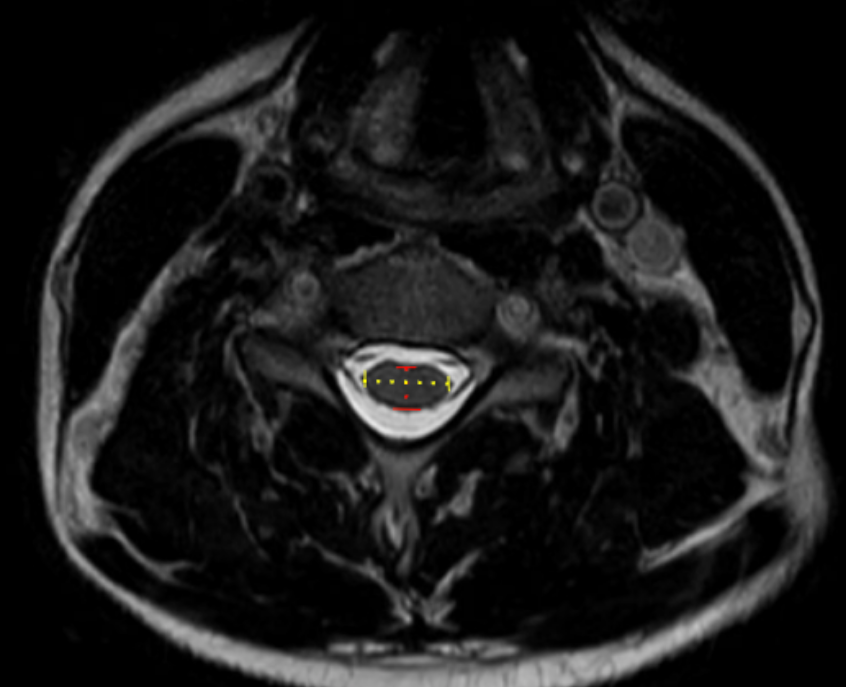

Compression Ratio (AP diameter transverse diameter of cord)

The compression ratio is a morphometric MRI parameter that quantifies the degree of cervical spinal cord deformation by comparing the anteroposterior (AP) diameter of the cord to its transverse (left–right) diameter on axial imaging.

This ratio reflects the shape distortion of the spinal cord rather than absolute size alone. A reduced compression ratio indicates flattening of the cord, which is commonly seen in degenerative cervical myelopathy, disc–osteophyte complexes, ossification of the posterior longitudinal ligament (OPLL), and chronic canal stenosis. The compression ratio correlates with neurologic deficit severity and functional outcomes, often complementing cord cross-sectional area (CSA) and canal measurements.

• Measure the Anteroposterior (AP) cord diameter:

• Draw a straight line from the anterior surface of the cord to the posterior surface of the cord.

• Ensure the line is perpendicular to the transverse axis.

• Measure the Transverse (left–right) cord diameter:

• Draw a straight line across the widest horizontal dimension of the cord at the same level.

• Calculate the Compression Ratio:

Compression Ratio = AP Cord Diameter/Transverse Cord Diameter